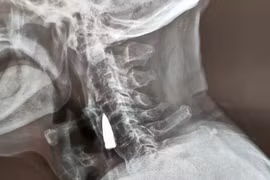

Các bác sĩ chụp X-quang ở Trung Quốc vô cùng sửng sốt khi phát hiện một viên đạn găm trong cổ của một cựu binh quân đội gần 80 năm và ông ấy không hề nhận ra nó còn ở đó.